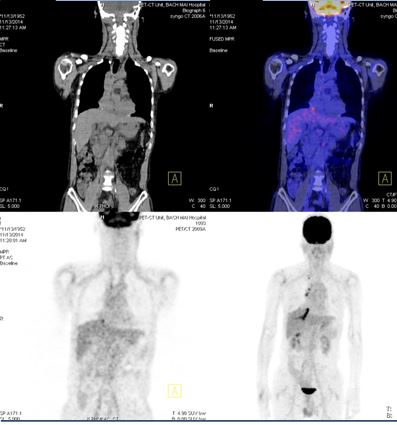

8.Đánh giá sau 9 tháng điều trị:

Lâm sàng đáp ứng tốt, bệnh nhân không còn nổi ban ngoài da, chụp PET/ CT đánh giá lại sau 9 tháng điều trị kết quả: khối u phổi phải không còn, không còn hạch di căn, các vị trí di căn tại gan, xương biến mất.

Trước điều trị ( T2/ 2014)

Sau điều trị 9 tháng ( T11/ 2014)

-          Bệnh nhân nam, 62 tuổi, chẩn đoán: K phổi phải giai đoạn muộn, T2N3M1, giải phẫu bệnh: ung thư biểu mô tuyến, đột biến EGRF dương tính.

-          Phương pháp điều trị: Thuốc điều trị đích: Iressa 250mg, uống 1 viên/ ngày, trợ gan.

Đánh giá sau 9 tháng điều trị: Bệnh đáp ứng hoàn toàn.